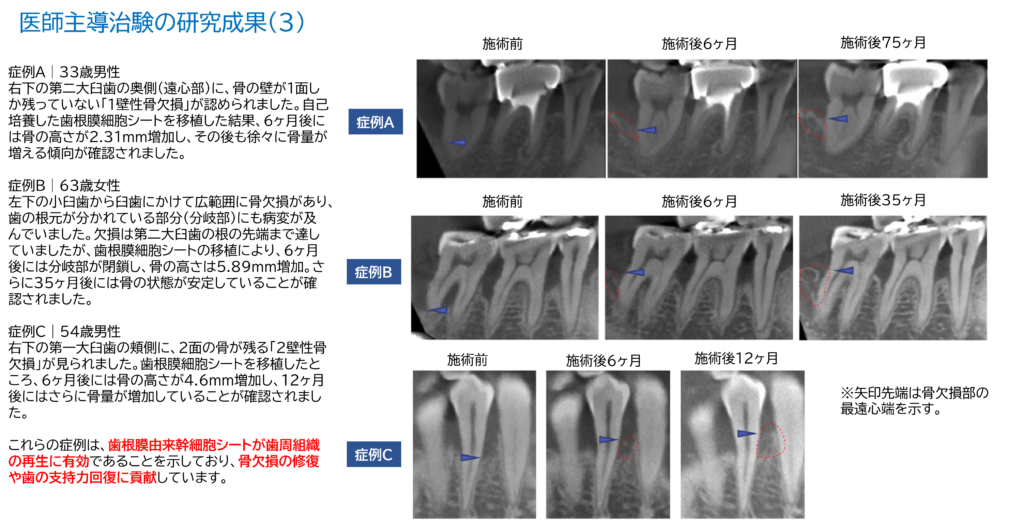

医師主導治験の研究成果(3)

症例A|33歳男性

右下の第二大臼歯の奥側(遠心部)に、骨の壁が1面しか残っていない「1壁性骨欠損」が認められました。自己培養した歯根膜細胞シートを移植した結果、6ヶ月後には骨の高さが2.31mm増加し、その後も徐々に骨量が増える傾向が確認されました。

※矢印先端は骨欠損部の最遠心端を示す。

症例B|63歳女性

左下の小臼歯から臼歯にかけて広範囲に骨欠損があり、歯の根元が分かれている部分(分岐部)にも病変が及んでいました。欠損は第二大臼歯の根の先端まで達していましたが、歯根膜細胞シートの移植により、6ヶ月後には分岐部が閉鎖し、骨の高さは5.89mm増加。さらに35ヶ月後には骨の状態が安定していることが確認されました。

症例C|54歳男性

右下の第一大臼歯の頬側に、2面の骨が残る「2壁性骨欠損」が見られました。歯根膜細胞シートを移植したところ、6ヶ月後には骨の高さが4.6mm増加し、12ヶ月後にはさらに骨量が増加していることが確認されました。

これらの症例は、歯根膜由来幹細胞シートが歯周組織の再生に有効であることを示しており、骨欠損の修復や歯の支持力回復に貢献しています。